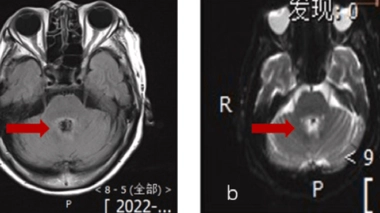

Elle pensait souffrir d'un cancer, elle avait en fait une amibe mangeuse de cerveau

Une lésion dans le cerveau est visible sur les examens